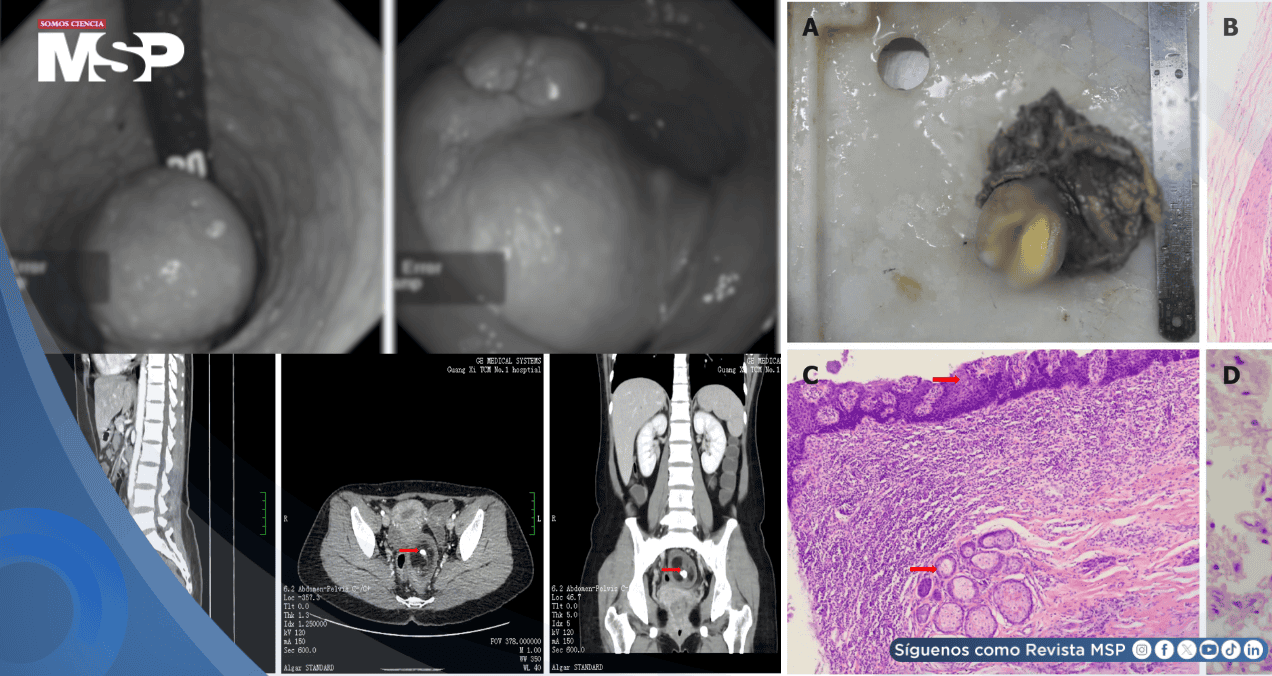

El examen reveló una masa de 4 cm × 3 cm × 3 cm dentro del ano, a unos 6 cm de la línea dentada, lisa al palparla y no dolorosa al exteriorizarse. Los análisis de laboratorio, como hemograma completo, electrolitos séricos, gonadotropina coriónica humana y panel metabólico, resultaron normales.

Sin embargo, la tomografía computarizada (TC) mostró una lesión redonda de 6,3 cm × 4,7 cm × 5,1 cm en la pelvis, con sombra escamosa de baja densidad, calcificación central, realce leve periférico y límites claros, sugestiva de teratoma; además, se observó un quiste anexial bilateral de baja densidad.

El examen patológico identificó dos tumores conectados en mucosa y serosa intestinal, de 6 cm × 5 cm × 4 cm y 2 cm × 2 cm × 2 cm, respectivamente. Microscópicamente, contenían piel con anejos, glándulas, grasa, tejido óseo, médula ósea y cerebral, confirmando un teratoma rectal maduro.

Los márgenes quirúrgicos estaban libres de tumor, y de seis ganglios linfáticos examinados, ninguno mostró metástasis (0/6).